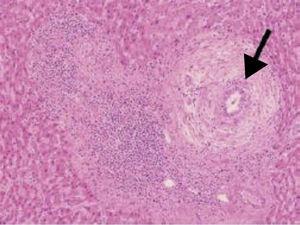

Biopsia hepática con lesión florida del conducto biliar (degeneración del epitelio ductal biliar con obliteración ductal focal y formación de granulomas) (fig. 1).

Figura 1.a. Se observa un granuloma epitelioide en un tracto portal, rodeado de infiltrado linfoplasmocitario (los granulomas no son típicos de HAI clásica). b. Destrucción de ductos biliares interlobulillares. c. Colangitis no supurativa crónica destructiva (flecha) e infiltrado de interfase y lobulillar (asterisco).